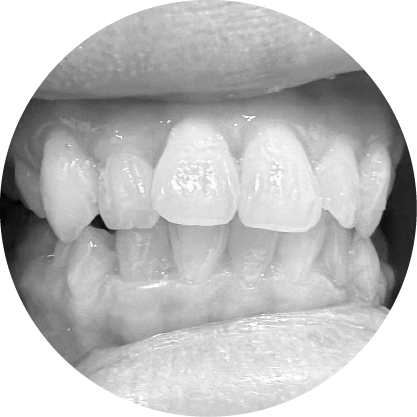

ตัวอย่างในชีวิตจริง

ฟันหน้ายื่น (ฟันสบลึก)

แก้ไขฟันสบลึก เพื่อรอยยิ้มที่สมดุล

ฟันสบลึกเกิดขึ้นเมื่อฟันบนยื่นทับฟันล่างมากเกินไป หากปล่อยไว้โดยไม่รักษา อาจส่งผลต่อรูปลักษณ์และสุขภาพช่องปาก การรักษาทางทันตกรรมจัดฟันมีเป้าหมายเพื่อฟื้นฟูความสมดุลและการทำงานของฟัน เพื่อให้คุณมีรอยยิ้มที่มั่นใจ